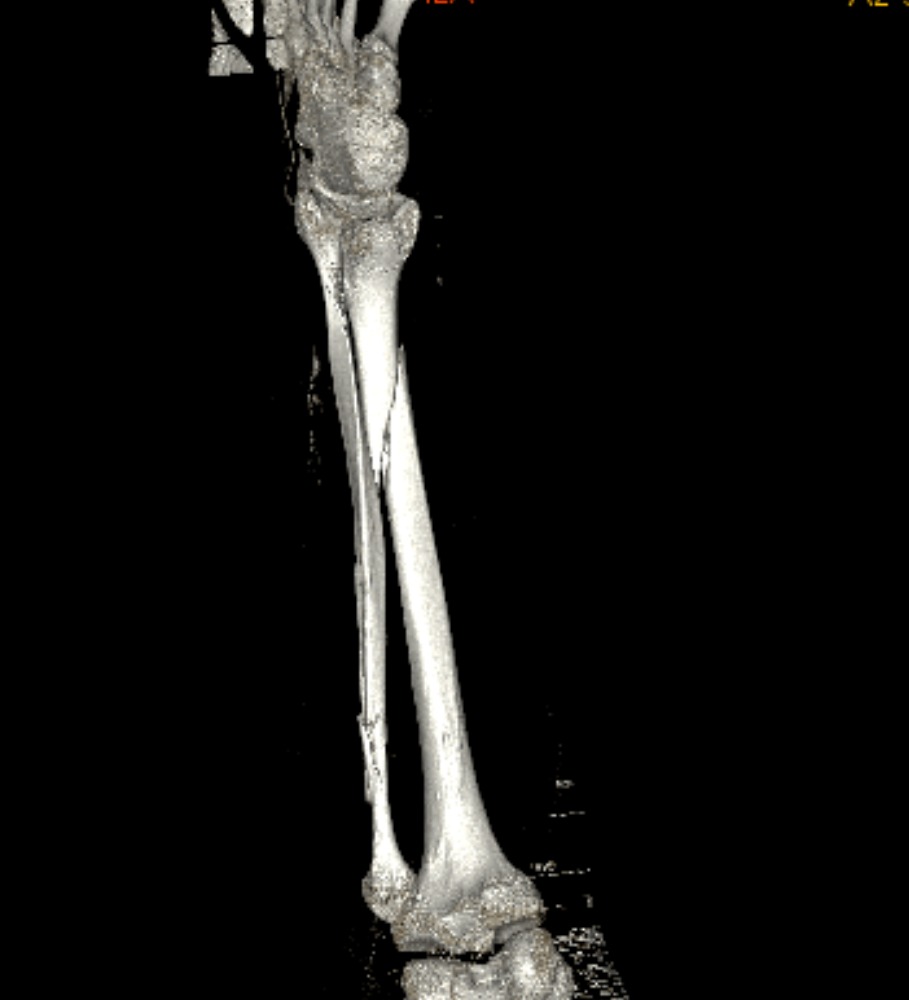

Bij deze mijn ervaring van 9 okt 2025